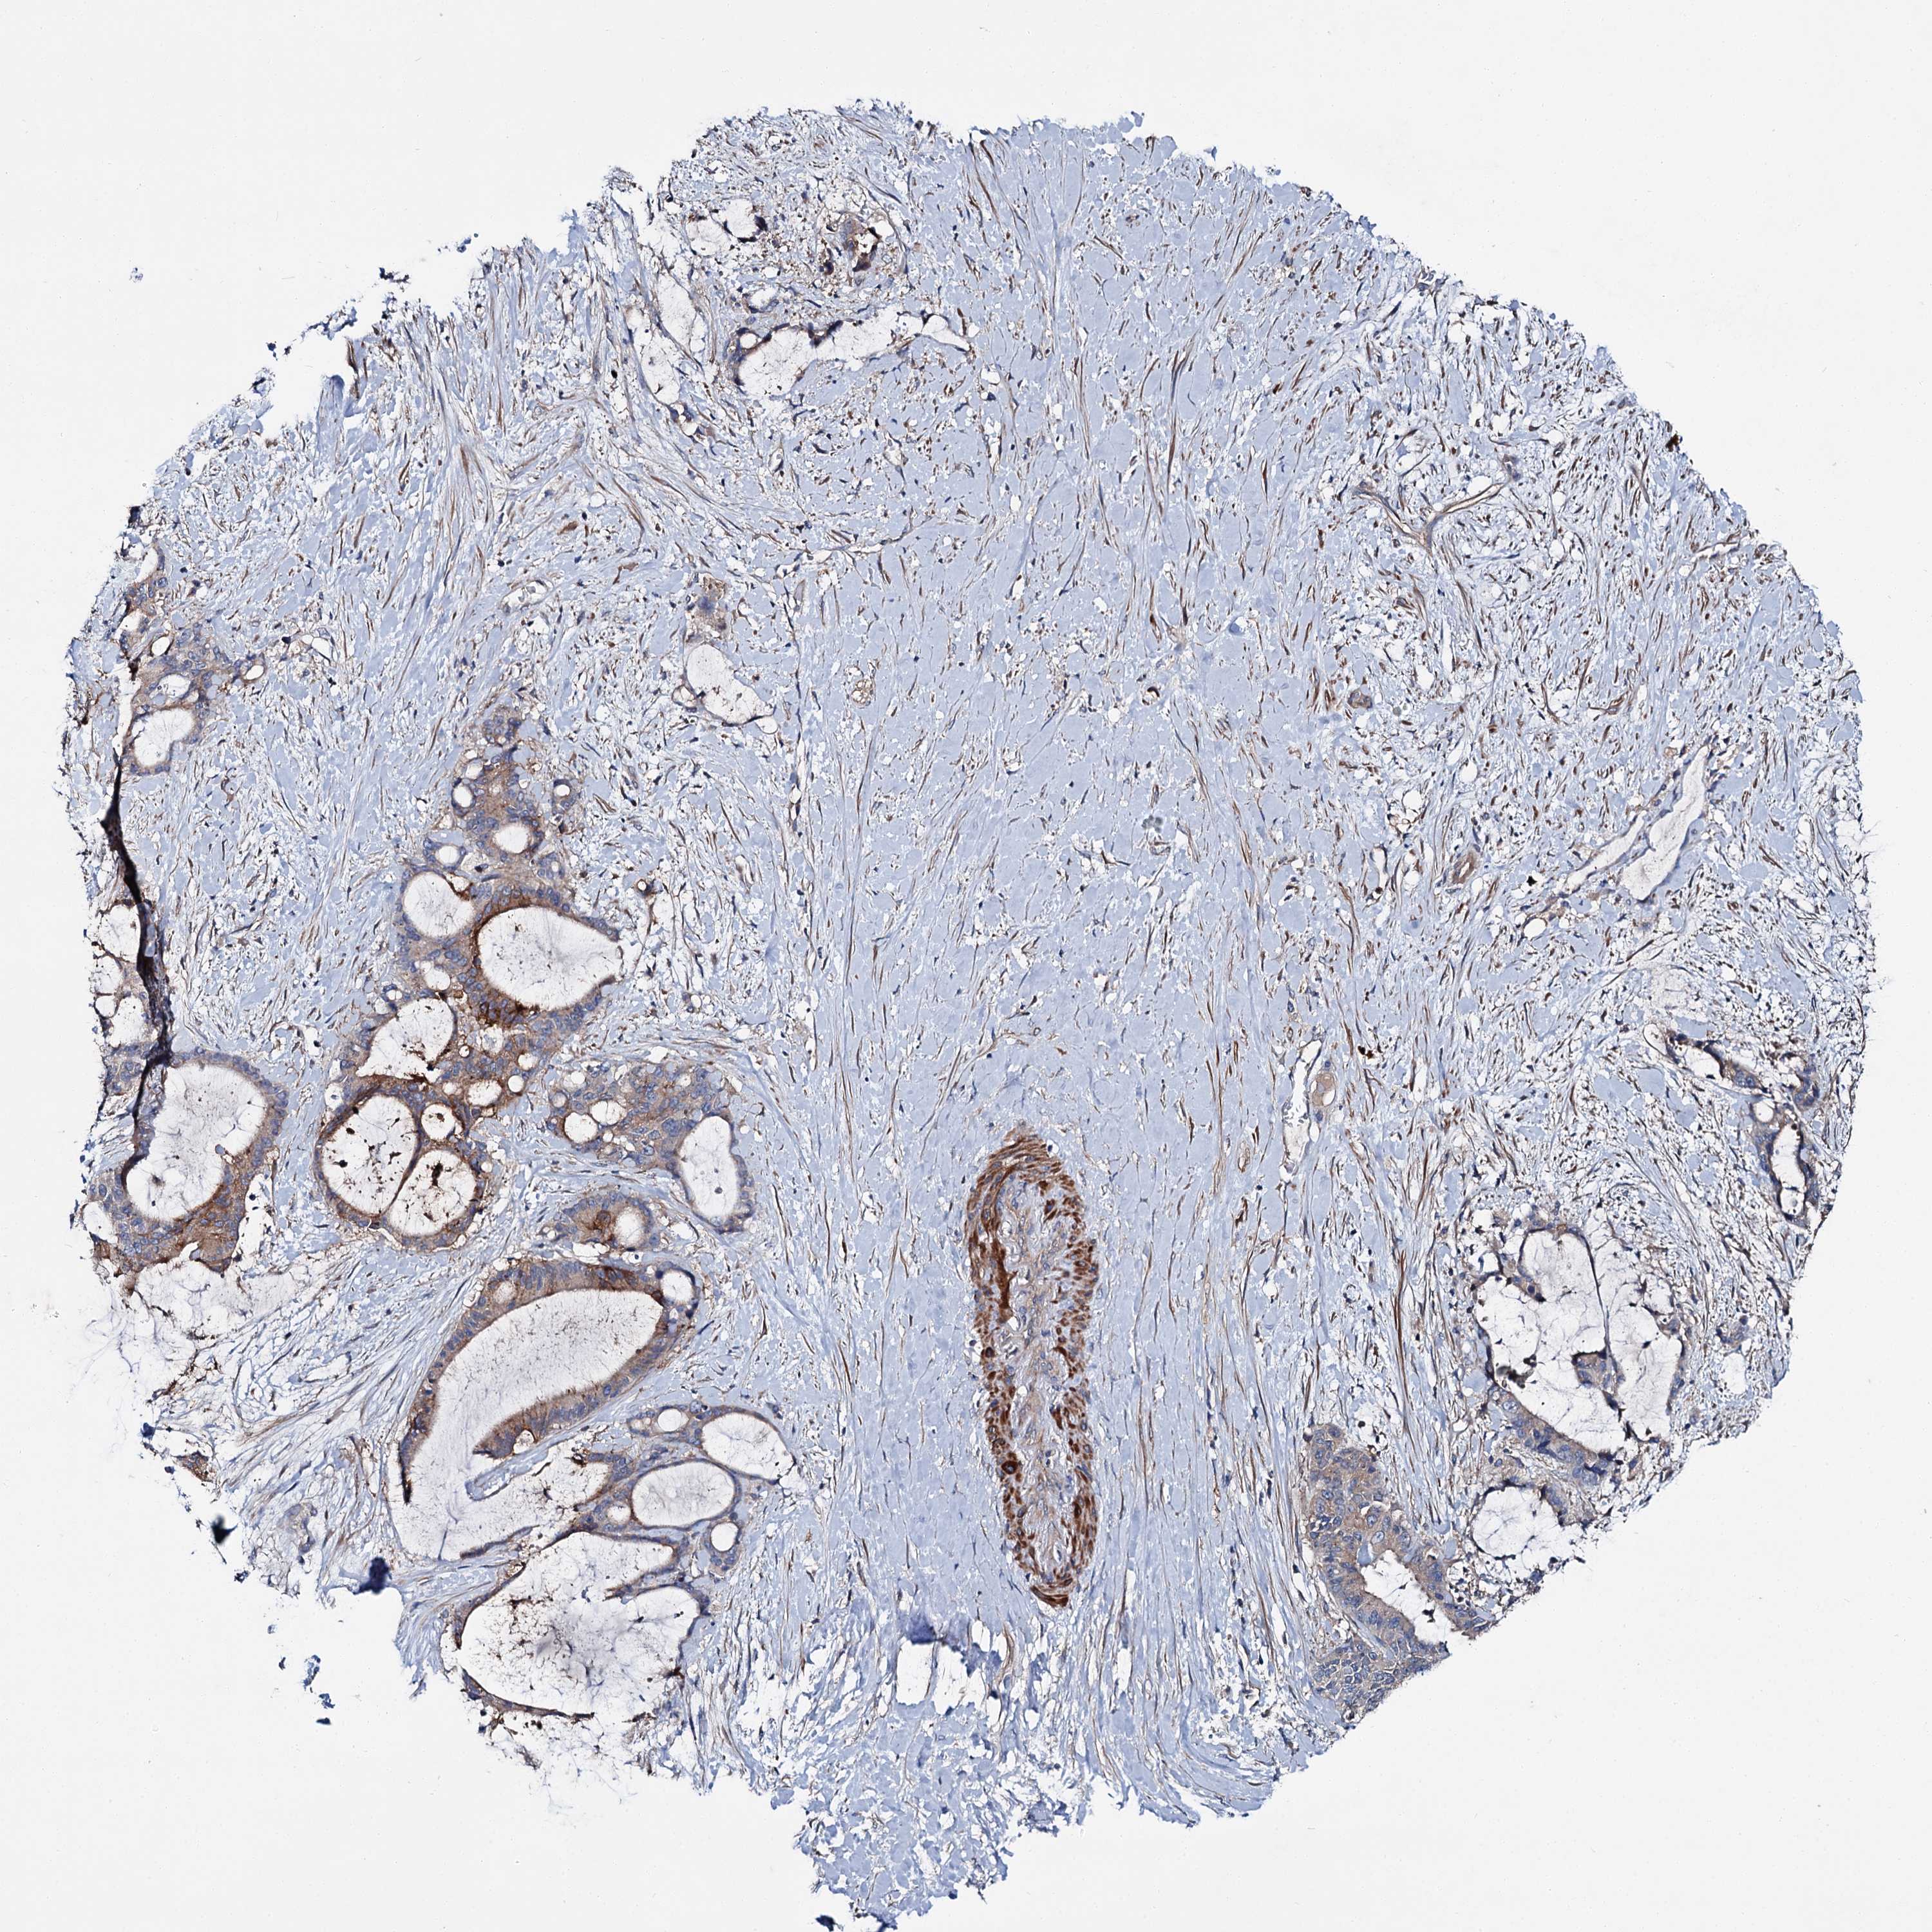

LIVER CANCER - Protein expressioni

A mouse-over function shows sample information and annotation data. Click on an image to view it in a full screen mode. Samples can be filtered based on level of antibody staining by selecting one or several of the following categories: high, medium, low and not detected. The assay and annotation is described here.

Note that samples used for immunohistochemistry by the Human Protein Atlas do not correspond to samples in the TCGA dataset.

Antibody stainingi

Antibody staining in the annotated cell types in the current human tissue is reported as not detected, low, medium, or high, based on conventional immunohistochemistry profiling in selected tissues. This score is based on the combination of the staining intensity and fraction of stained cells.

Each image is clickable and will lead to virtual microscopy that enables deeper exploration of all samples and also displays staining intensity scores, fraction scores and subcellular localization as well as patient and tissue information for each sample.

Antibody HPA039390

Staining

High

Medium

Low

Not detected

Intensity

Strong

Moderate

Weak

Negative

Quantity

>75%

75%-25%

<25%

None

Location

Nuclear

Cytoplasmic/membranous

Cytoplasmic/membranous,nuclear

Cholangiocarcinoma

Carcinoma, Hepatocellular, NOS